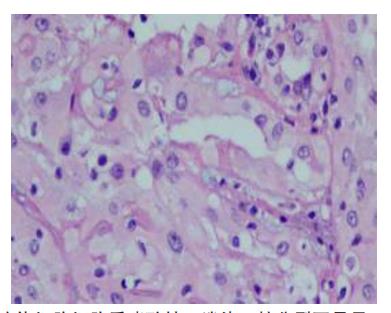

图5 低倍镜下细胞呈腺腔样排列,未见色素颗粒(HE,×100)

Figure 5 The tumor cells are arranged in glandular luminal and no pigment granules were seen (HE, ×100)

biomicroscopy,UBM)显示虹膜根部向前膨隆与角巩膜缘相贴,局部方向虹膜后见中等回声隆起(图3 )。临床诊断:左眼虹膜睫状体肿物,左眼并发性白内障。于2021年12月23日行“虹膜睫状体肿物切除术,左眼白内障超声乳化抽吸术”,术中左眼6点位睫状体部可见大小约3 mm灰黄圆形隆起,表面光滑,部分与晶状体轻微粘连,易剥离。手术中切除的肿瘤组织(图4)行常规病理检查:苏木精-伊红(hematoxylin-eosin,HE)染色可见肿瘤低倍镜为边界清楚的结节状,细胞呈腺腔样排列,部分为条索状,瘤细胞细胞质嗜酸性,淡染,未见色素颗粒(图5);部分间质黏液样变性,瘤细胞间见均匀红染的基底膜样物(图6)。高倍镜下瘤细胞胞核呈圆形或卵圆形,染色质分布均匀,偶可见小核仁,未见核分裂。过碘酸雪夫(periodic acid-SchiffPAS)染色瘤细胞间基底膜样物为阳性( 图 7 ) 。免疫表型:肿瘤细胞表达 S-100 、Vimentin、CK8/18、EMA、CKpan、Melan-A,Ki-67标记指数为5%,而GFAP、CEA、P63、HMB-45均为阴性(图8~10)。病理诊断:左眼ANPCE。手术后查体:右眼远视力1.0,左眼远视力0.06;右眼矫正视力:+0.5ODS→1.0,左眼矫正视力:矫正无助;右眼眼压:13 mmHg,左眼眼压:6 mmHg;术眼结膜充血水肿(++),角膜后弾力层褶皱明显减轻,前房深度可,瞳孔竖椭圆形,直接对光反射消失,晶体缺如。截至随访日期,术后3个月无疾病进展。